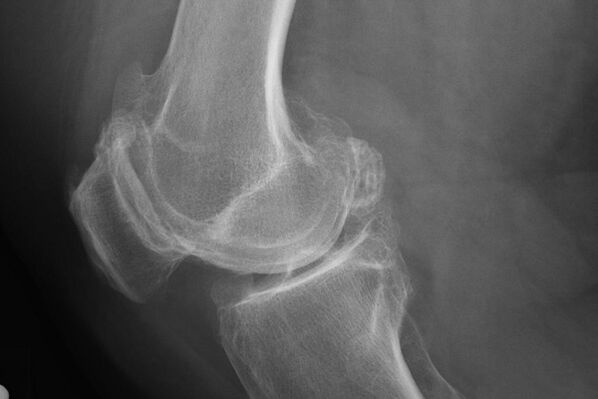

Як правіла, дыягназ хваробы на гэтай стадыі ўзнікае выпадкова падчас X -RAY. На ім лекар можа адзначыць некаторыя парушэнні на храстках. Таксама можна звузіць прасвет паміж часткамі сустава.

X -ray дапаможа вызначыць адхіленні ў храстку.

Пасля абследавання лекар прызначае рэнтгенаграфію пацыента. Гэта асноўны метад дыягностыкі артрозу каленнага сустава любой ступені.

X -ray дае лекару ўяўленне пра змены, якія адбываюцца ў храстку сустава. Аднак у некаторых выпадках пачатковы этап не можа быць вызначаны на малюнку.

Пры неабходнасці лекар можа прызначыць неаднаразовы праход рэнтгенаўскай або вылічанай і магнітна-рэзананснай тамаграфіі.